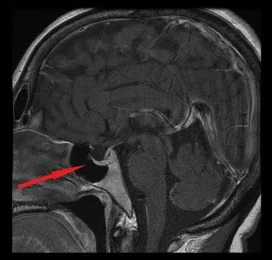

Το αδένωμα της υπόφυσης είναι η ανάπτυξη ενός καλοήθους όγκου στην περιοχή της υπόφυσης. Η υπόφυση είναι ένας αδένας που βρίσκεται στη βάση του εγκεφάλου, σε μία περιοχή που ονομάζεται «εφίππιο», και ο οποίος παράγει διάφορες ορμόνες, οι οποίες είναι σημαντικές για τη λειτουργία του σώματος (εικόνα 1). Διακρίνονται σε μικροαδενώματα (μέγεθος λιγότερο του ενός εκατοστού) και μακροαδενώματα (μέγεθος άνω του ενός εκατοστού). Υπάρχουν διάφοροι τύποι αδενωμάτων της υπόφυσης, ανάλογα με το ποια κύτταρα εμπλέκονται.

Απεικονιστικός έλεγχος, δηλαδή απεικόνιση των δομών του εγκεφάλου, κυρίως με μαγνητική τομογραφία. Σε μερικές περιπτώσεις μακροαδενωμάτων, ενδεχομένως να χρειάζεται και αξονική τομογραφία.